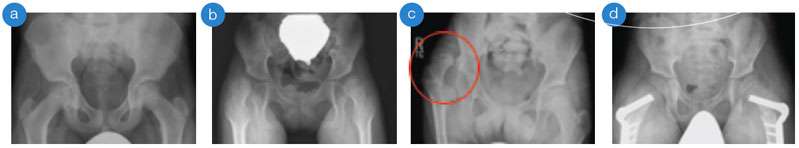

(a) normal hips and pelvis, (b) subluxated/partially dislocated hips, (c) right dislocated hip (circle), (d) after surgical correction of subluxated hips with plates and screws

Typically, certain muscles are more spastic than others. This muscle imbalance, combined with delayed weight bearing, may lead to hip dislocation, when the top of the femur (thigh bone), moves out of the hip socket. Hip dislocation in children with cerebral palsy is associated with difficulties in sitting, personal care and hygiene and pain or scoliosis (curvature of the spine) may occur. The team at the UCLA/LOIC CCP is committed to preventing hip dislocations in children with cerebral palsy by performing regular exams and obtaining x-rays over time. This is called hip surveillance. Our method of hip surveillance is based on evidence and best practice from clinicians around the world.

- Surgical release of spastic muscles for “hips at risk” – hips that are partially dislocated, or “subluxated”, to prevent full dislocation

- Surgery of the hip and pelvic bones for more severely affected hips (those with a greater amount of subluxation) in older children